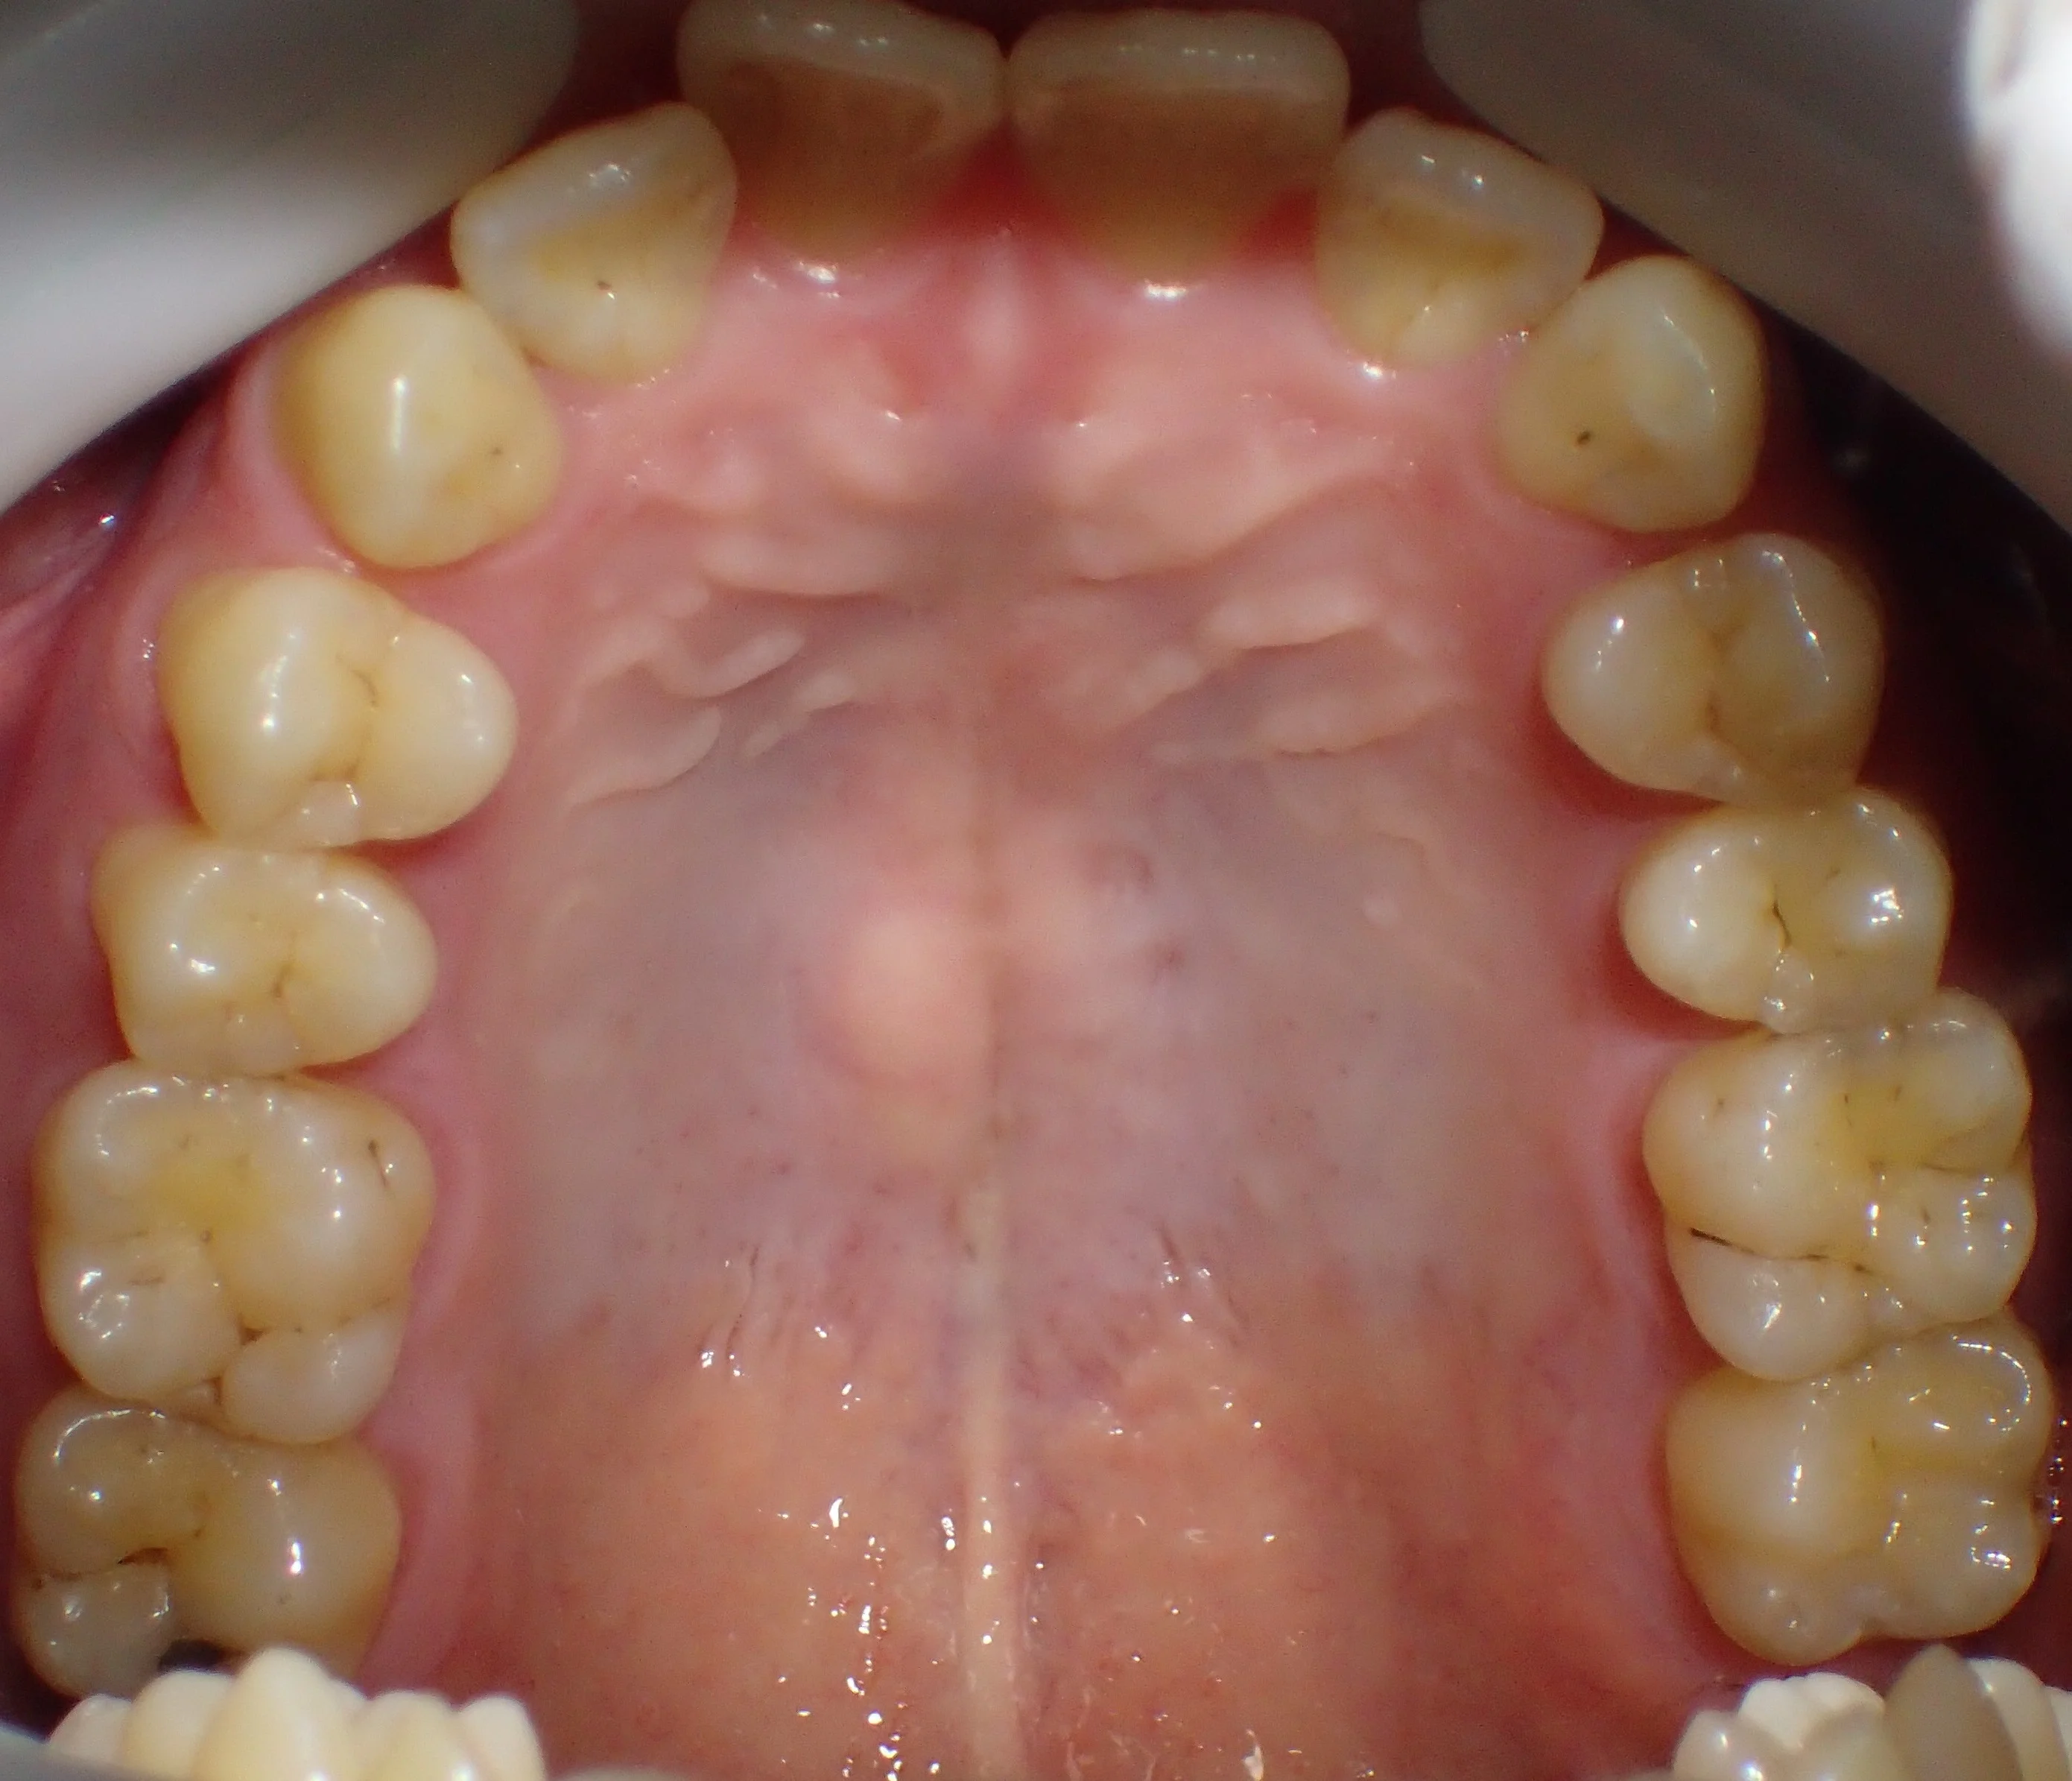

まだ坂寄歯科医院には全顎的にダイレクトボンディングで治療した症例がありませんので、前の医院にて治療を完了された方の写真を載せたいと思います。

鏡面像で反転済みです。

「向こう側からこちらに向かって口を開いているイメージ」ですね。

どこを治療したかわかりますか?

答えは下の方に書いておきますので、スクロールしてください。